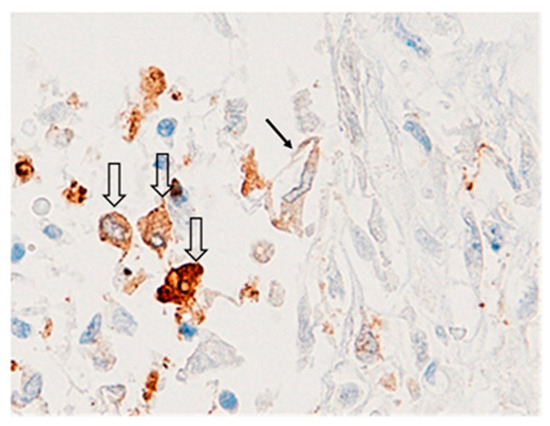

2.4. GAL-3 Macrophages Depletion Is Associated with Persistence of Viral Spike-1 Sequence in COVID-19 Lethal Lungs